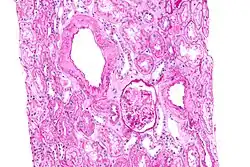

Amylose rénale

L’amylose rénale est de loin la plus précoce et la plus fréquente des complications

La substance amyloïde de la maladie périodique est formée de fibrilles identiques à la protéine de l'amylose AA, et elle intéresse de manière diffuse la paroi de toutes les artérioles, sauf celles du système nerveux central ; cette répartition est dominée par la localisation rénale..

La survenue d’une amylose au cours de la maladie périodique transforme une affection invalidante mais bénigne en une maladie mortelle quasi certaine. Son incidence est élevée chez les Juifs originaires d’Afrique du Nord et chez les Turcs et plus faible chez les Arméniens, les Arabes et les Juifs ashkénazes[1].

Son évolution passe par deux phases principales. Le début est asymptomatique, il s'agit d'une protéinurie modérée, de durée moyenne de 3 à 4 ans. Son apparition au cours de la maladie périodique constitue une très forte présomption d’amylose, et cette protéinurie doit être recherchée au moins une fois par an[31].

La phase néphrotique est caractérisée par l’apparition d’un syndrome néphrotique clinique et biologique. La confirmation histologique peut être apportée par la biopsie rénale, la biopsie rectale (positive dans 75 à 85 % des cas), voire par la biopsie médullaire.

Elle laisse place, après en moyenne 1 ou 2 ans d’évolution, à la phase urémique avec insuffisance rénale, qui progresse en règle rapidement, pour atteindre son stade terminal 12 à 18 mois plus tard.